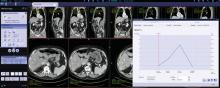

Imaging is pivotal for detection, staging and evaluation of tumor response to treatment. It is instrumental in determining which treatment is best suited to a patient and may be used to help guide surgery and radiation therapy. With chemotherapy, follow-up imaging exams are used to track tumor response and determine if different drugs should be used.